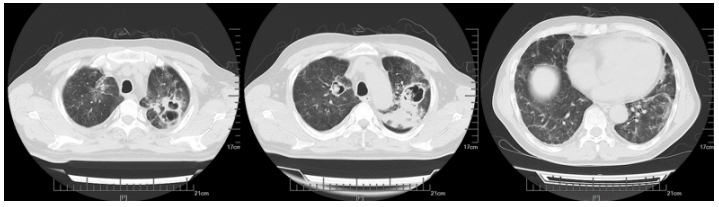

1月30日开始发热,热峰39℃,伴夜间呛咳。2月1日痰中带血,脓血痰,偶伴小量咯血(10 ml左右)。2月2日胸部CT可见空洞病灶进展(图4)

图4  复查胸部CT(2023-02-02)

患者热峰下降, 但体温仍有波动。2月9日复查胸部CT见右上肺病灶吸收, 左上肺进展(图5)。患者仍间断发热, 热峰38℃, 伴脓血性痰液。

图5  复查胸部CT(2023-02-09)

3月1日胸部CT见两肺病灶较前吸收(图7)。病情得到改善。

图7  复查胸部CT(2023-03-01)